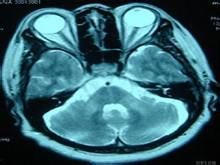

常染色體顯性小腦性共濟失調(autosomaldominantcerebellarataxia,ADCA)種類很多。病理改變累及小腦及其傳入和傳出徑路,除有小腦神經元脫失外,也可見脊髓、腦橋、橄欖核,基底節、視神經、視網膜及周圍神經病變,臨床特點是進行性軀幹共濟失調、構音障礙、辨距不良,意向震顫等單純小腦症狀,也可見不自主運動,視覺或聽覺障礙、眼外肌麻痹、錐體束征,感覺異常、腦神經麻痹等。常見各種臨床症狀的組合:單純小腦征,小腦征和腦幹征、小腦和基底節綜合徵、脊髓或周圍神經病徵,小腦征和特殊感覺(聽、視)障礙、小腦和垂體功能障礙,小腦和肌陣攣綜合徵、小腦和錐體性肌張力增高等。

Machado-Joseph病(MJD)的特點是運動系統進行性變性,即小腦系統、錐體系統、錐體外系統和前角運動單位有廣泛變性,現認為MJD是最常見的脊髓小腦變性病,中國也有報導(Zhou等,1997)。

小腦齒狀核及紅核變性,黑質和紋狀體有神經元脫失,錐體束和周圍運動單位也有變性,最終全部運動系統變性。